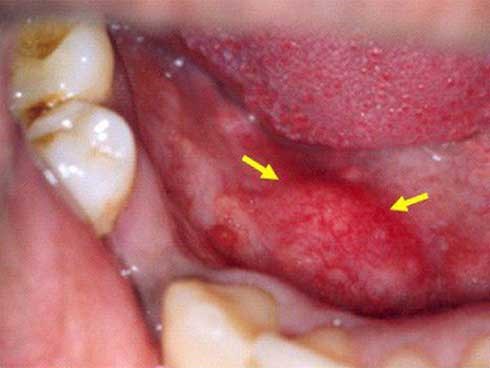

Bác sĩ cho rằng dấu hiệu có kinh nguyệt (chảy máu âm đạo) của bà Hoàng không phải do kinh nguyệt mà là do 2 chứng bệnh này.

Những căn bệnh ung thư lạ lùng ít người biết

Có một số dạng ung thư mà ít người trong chúng ta đã từng nghe đến.